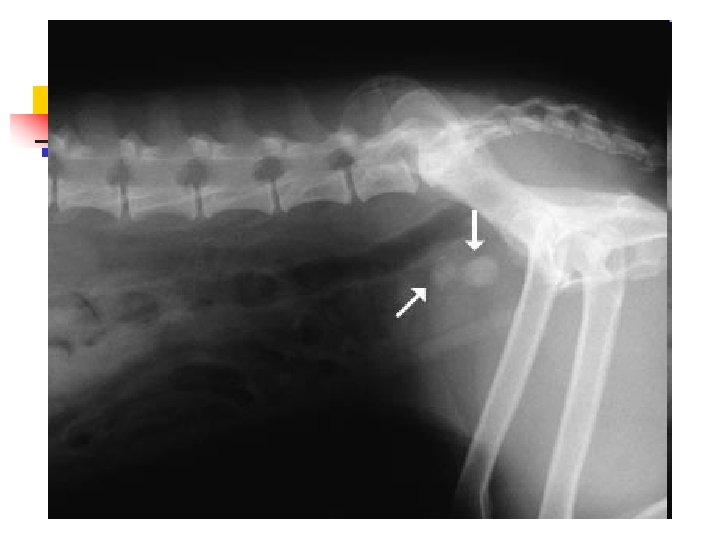

When Animals Limp n n n The good new is that 9 out of 10 limping animals have what we call soft tissue injuries a sprain, a pull, a bruise and only require exercise restriction to heal. However, 1 out of 10 animals with lameness has something more serious, and we can tell which ones by close observation of the patient walking and careful physical examination. In those cases, radiographs are used to make a diagnosis.

Hip Dysplasia n n Hip dysplasia is a looseness in the hip joint. The hip is a ball-and-socket joint and the head (ball) of the femur (thigh bone) normally should be deep within the hip socket. When hip dysplasia is present, the ball moves in and out of the socket with ease. Over time arthritis (degenerative joint disease, osteoarthritis) sets in as the body tries to stabilize the loose joint.

When Lameness isn’t Simple n n Sometimes when an animal limps the cause turns out to be something more serious than a simple injury. The doctors palpated a firm, painful lump in the leg this dog was favoring. Radiographs showed that the bone was expanded in that area, with a motheaten, hollowed-out center. These are classic signs of a tumor in the bone, known as an osteosarcoma.